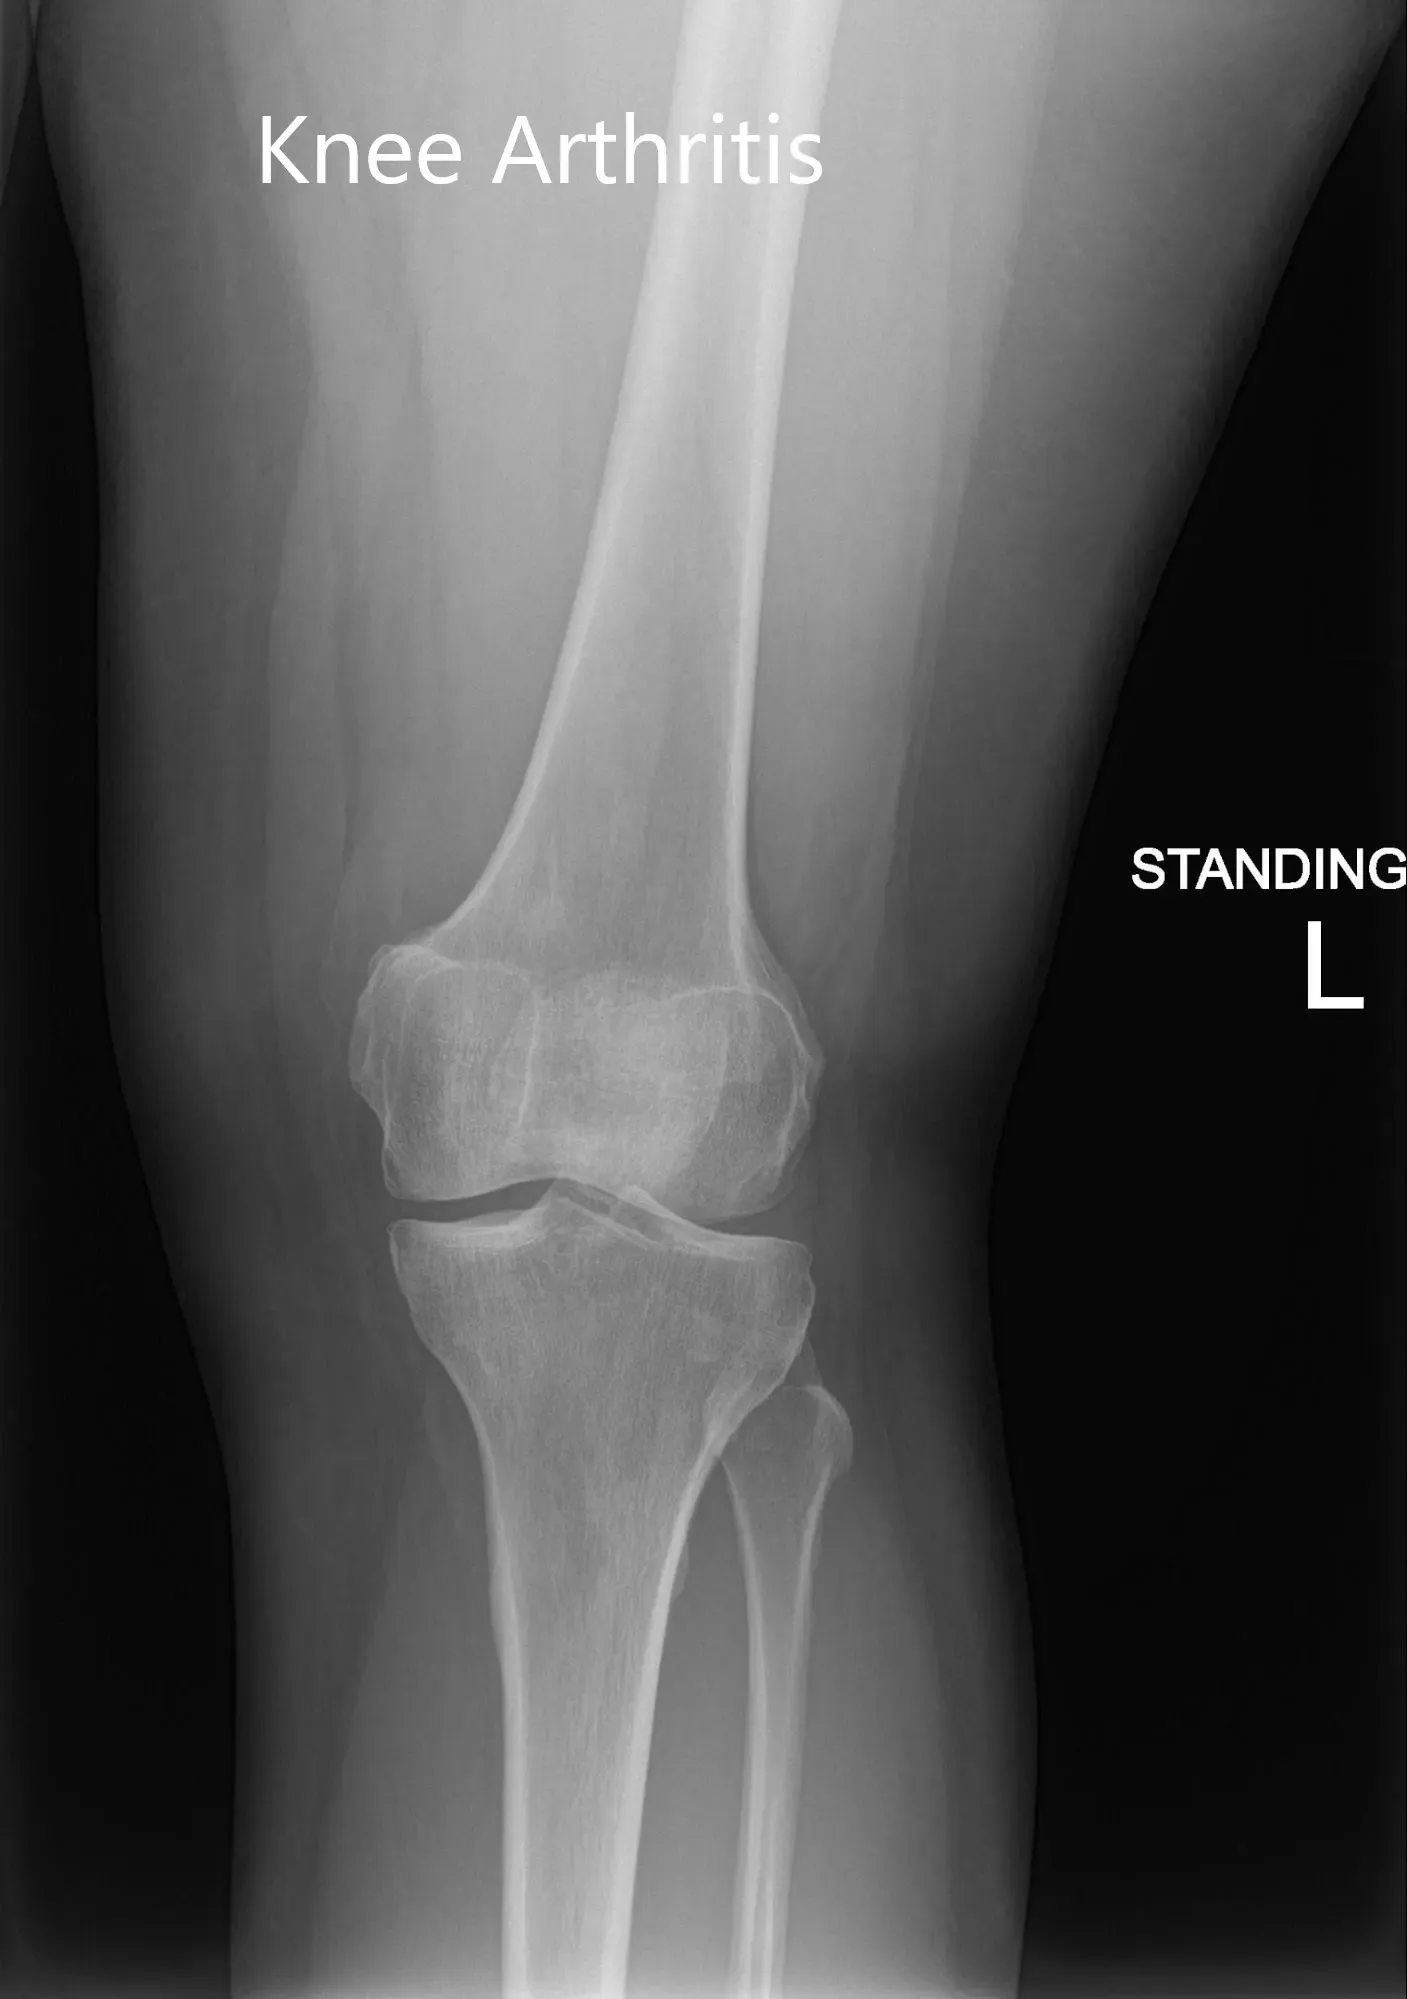

Su examen físico reveló sensibilidad en la línea articular medial con inflamación leve. La rodilla no mostró inestabilidad en las pruebas de esfuerzo anterior, posterior, valgo y varo. Las imágenes revelaron artritis postraumática en la rodilla izquierda. Le pusieron una inyección de cortisona en la rodilla con un excelente control del dolor. Posteriormente, el paciente fue seguido en 3 meses.

Radiografía preoperatoria de la rodilla izquierda que mostró imágenes AP y laterales

Se realizó una tomografía computarizada preoperatoria de la rodilla izquierda del paciente para evaluar su biomecánica y anatomía. Los datos se utilizaron después para obtener imágenes 3D de la rodilla del paciente, ayudando a construir implantes e instrumentos únicos específicos de cada paciente. El reemplazo personalizado de rodilla ofrece una cirugía que preserva los huesos. Los implantes únicos específicos para el paciente aseguran la restauración de la superficie articulada natural y la geometría de la rodilla.